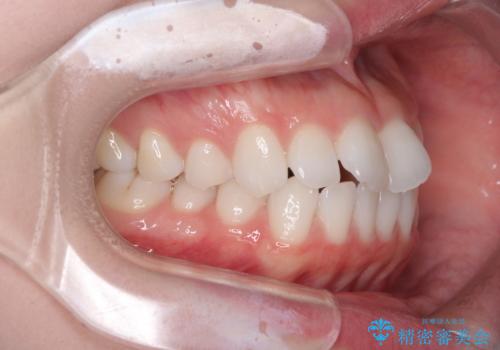

- 海外留学を前に上下のデコボコと奥歯の咬み合わせを改善したいとのことで来院された患者様です。

期間が限られていたため、ワイヤー装置による矯正治療を行うこととしました。

治療開始から4ヶ月ほどで概ね歯列が整い、その後の3ヶ月で細かい部分を仕上げていきました。

短期間で綺麗に仕上がり、患者様には大変満足していただきました。